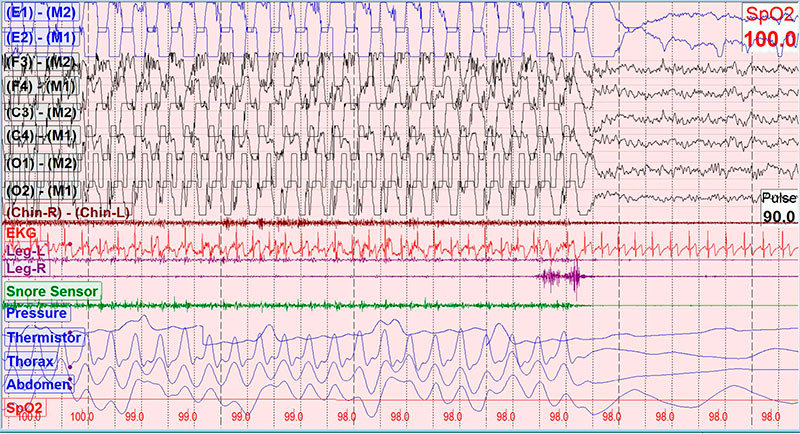

The lowest oxygen saturation was 92% and the mean EtCO2 was 31 mmHg. The periodic limb movement index was 0.9 events per hour. There were 46 episodes of whole body rocking behavior during transitions to sleep with the longest episode being 187 seconds. Three representative 30 seconds epochs from the patient’s polysomnogram are shown in the Figures

Figure Legend

30-second epochs recorded during wakefulness in the supine position. Panels A, B, and C show the onset, continuation, and termination of a typical event, respectively.

Polysomnography (PSG) is often performed to verify the diagnosis and rule out other causes of the behavior. Characteristic findings include a minimum and maximum movement frequency of 0.5 and 2 Hz, respectively, a minimum of 4 rhythmic movements in a cluster and minimum amplitude on the electromyography (EMG) of a rhythmic burst twice the background EMG activity (3). Time synchronized video PSG is recommended to help make the diagnosis (4).

Rhythmic movements occur most often during N1 and N2 sleep, though they can occur with drowsiness (1). In the patient described here, almost all of the rhythmic movements occurred during wake-sleep transitions or N2 sleep, and were not associated with infrequent respiratory events.